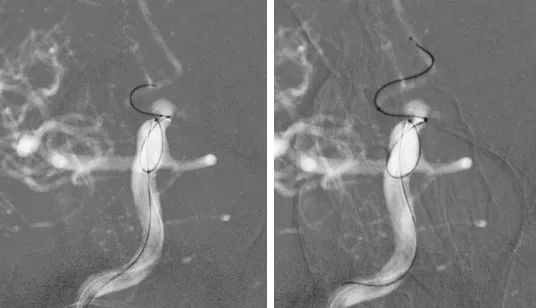

全脑血管造影:右侧大脑中动脉M1分叉处动脉瘤,瘤体3.3 mm*4.1 mm,瘤颈2.7 mm。前交通动脉瘤栓塞完全。

全麻满意后,常规消毒铺巾,采用改良 Seldinger技术穿刺右侧股动脉成功,置入6F动脉鞘。黑泥鳅导丝带领5F单弯导管行脑动脉造影,右侧颈内动脉造影见:右侧大脑中动脉M1分叉处动脉瘤,瘤体3.3 mm*4.1 mm,瘤颈2.7 mm。前交通动脉瘤栓塞完全。

经右侧股动脉鞘,黑泥鳅导丝带领导引导管(Codman 6F Envoy DA)到达右侧颈内动脉岩段,微导丝(Synchro--14 0.014 in*200 cm)带领支架微导管(Excelsior SL--10)到达右侧大脑中动脉M2段,退出微导丝。微导丝带领弹簧圈微导管(Echelon10)到达右侧M1远端分叉处动脉瘤内,退出微导丝。经弹簧圈微导管填入弹簧圈(Codman 3 mm*4 cm)经支架微导管输送支架(Neuroform Atlas 3.0 mm*15 mm)并释放在M2段至M段中部,完全覆盖动脉瘤颈。继续经弹簧圈微导管依次填入弹簧圈数枚,间断造影确保右侧大脑中动脉及远端血流通畅。右侧颈内动脉造影确认:动脉瘤致密填塞,载瘤动脉通畅,手术结束。有侧股动脉穿刺处用血管封堵器封堵,并压迫器持续压迫。术后患者麻醉清醒,拔除气管插管,呼唤应答,对答切题,言语清楚,四肢肌力肌张力正常。安返病房。